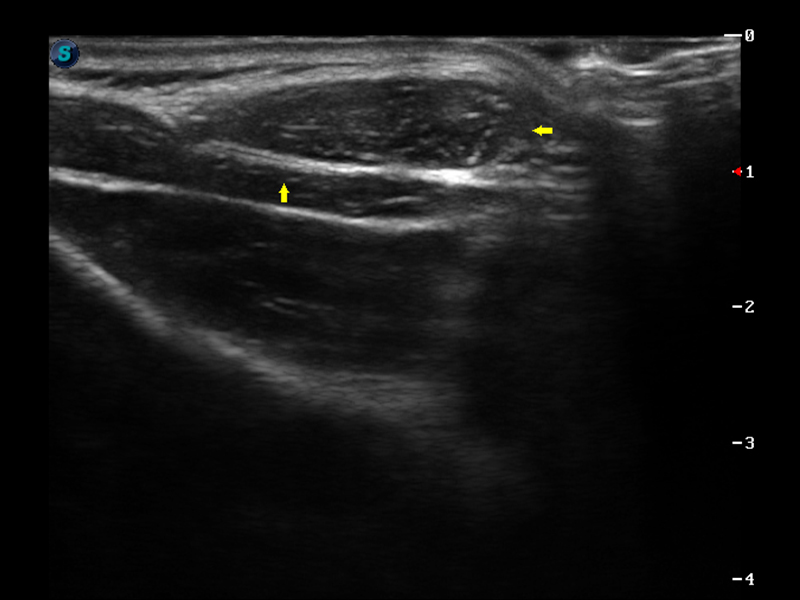

S9便携式彩色多普勒超声诊断仪是美狮贵宾会官网研发的高端便携彩超设备,外观设计新颖、产品性能卓越。S9在便携超声领域采用了突破传统的触摸屏交互设计,并以先进的软件硬件技术和设计理念,为您带来清晰的图像质量、稳定的工作性能和便捷的操作体验。